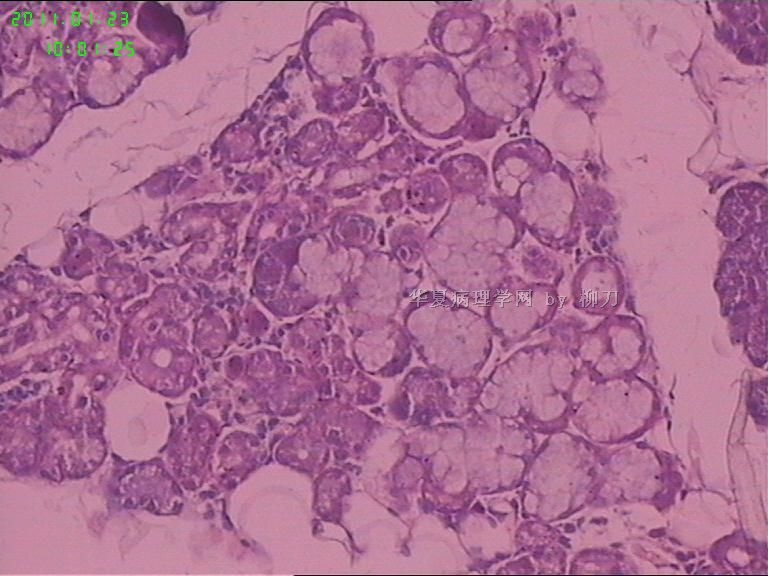

姓    名: ××× 性别:  男 年龄:  36

标本名称:  腮腺包块

简要病史:  包块2年多,数月来增大。

2,3图是前2个结节的镜下表现,梭形皮瓣是皮内痣。4以后是具完整包膜的肿块表现,核分裂少见。

我们考虑肌上皮瘤,少见多怪,老师们请多指教。

现有图像上看考虑肌上皮瘤。如果粘液样区域多,要考虑多形性腺瘤。

可以做一下组化:CK、SMA、S-100、GFAP、P63。

肌上皮瘤